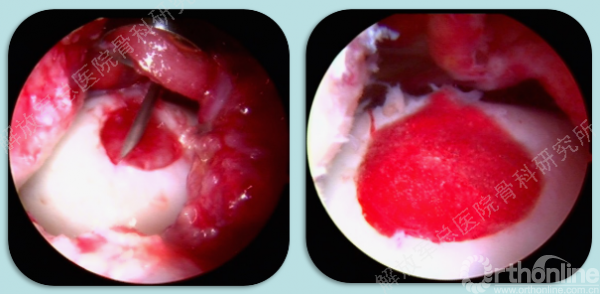

组织工程软骨镜下植入。

术后十天复查核磁证明关节镜下也是可行的。